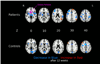

Psychotic disorders are characterized by significant deficits in attentional control, but the neurobiological mechanisms underlying these deficits early in the course of illness prior to extensive pharmacotherapy are not well understood. Moreover, little is known regarding the symptom and brain changes associated with amelioration of attentional impairments through antipsychotic pharmacotherapy. In this study 14 male patients experiencing a first-episode of psychosis with minimal prior antipsychotic treatment completed an attentional control task while undergoing functional magnetic resonance imaging at the onset of treatment with a second generation antipsychotic (risperidone or aripiprazole) in a double blind randomized clinical trial and then again following approximately 12 weeks of treatment. In addition, 14 age-, and performance-matched healthy male volunteers who were not treated completed the same task at a baseline timepoint and then again following 12 weeks. Patients showed significantly greater activation than healthy volunteers in the right globus pallidus, left thalamus, and right thalamus at the time of the baseline scan. Among patients there was a significant reduction in right globus pallidus blood-oxygen level dependent (BOLD) response following antipsychotic treatment that correlated significantly with improvement in response accuracy and reductions in thought disturbance. No changes in globus pallidus activation were observed in healthy volunteers over this time period. These preliminary findings suggest that improvement in attentional control and concomitant reductions in thought disturbance in first-episode psychosis may be associated with reductions in subcortical activity following administration of second-generation antipsychotics early in the course of illness. These findings have implications for understanding how changes in basal ganglia activity may be linked to improvements in attentional control through antipsychotics.